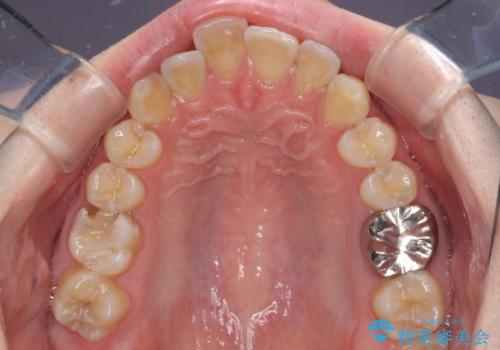

- 上下前歯のデコボコを気にして来院された患者様です。

マウスピース矯正でもワイヤー矯正でも対応可能でしたが、インビザラインによる自己管理が煩わしいとのことで、ワイヤー装置にて矯正治療を行うこととしました。

口元はやや突出感がありましたが抜歯矯正をするほどではないため、舌突出癖を改善するトレーニングをしっかりと行っていただき、現在よりも唇が閉じやすい位置に仕上げていくこととしました。

矯正治療後には気になっていた銀歯をセラミックで自然な色に仕上げました。